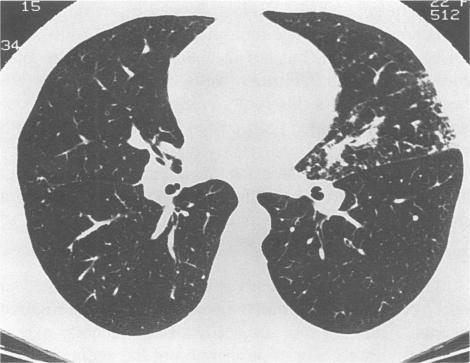

Sarcoidosis is a multisystem granulomatous disorder of unknown cause that presents most frequently in young adults with bilateral hilar adenopathy, pulmonary infiltrates, and skin or eye lesions. The multisystem clinical manifestations of this disease are a diagnostic challenge to all physicians. Although the clinical and pathologic characteristics of sarcoidosis are well described, the decision to treat and the optimal therapy are less well defined. This review focuses on the natural history, clinical manifestations, controversies in therapy, including steroid-sparing agents, and current concepts of how the disease's activity can be monitored.

结节病是一种病因不明的多系统肉芽肿性疾病,最常见于年轻成年人,表现为双侧肺门淋巴结肿大、肺部浸润以及皮肤或眼部病变。该疾病的多系统临床表现对所有医生来说都是一个诊断挑战。尽管结节病的临床和病理特征已有详尽描述,但关于治疗决策和最佳治疗方法的界定却不够明确。本综述聚焦于结节病的自然病程、临床表现、治疗方面的争议(包括糖皮质激素节省剂)以及目前关于如何监测该疾病活动的理念。